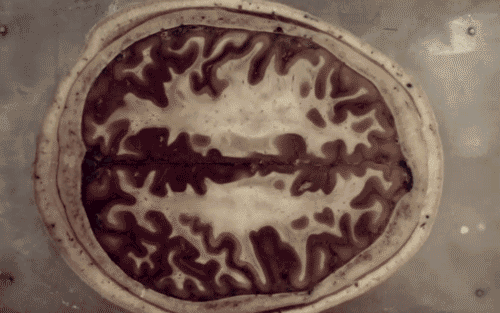

Nüüd on selge ka põhjus, miks see nii on, ja miks õppimine koolis sageli nõnda vaevaliselt käib. Neuroteadlased on ajupilte uurides leidnud mehhanismi, mis näitab, et stress ja ärevus takistavad normaalset õppimist.

Ajuosa, mida kutsutakse mandelkehaks, reageerib peamiselt hirmule ja ärevusele. Uuritud õpilased, kellel mandelkeha oli üleaktiveeritud, kurtsid pideva jõuetuse ja ärevuse üle. Neurokuvamise tehnoloogia abil, on võimalik näha, et neil lastel, kellel oli stressist põhjustatud mandelkeha ületalitlus, ei liikunud uus informatsioon mandelkehast edasi mällu ega ei moodustunud ka õpitu kohta uusi seoseid.